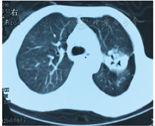

2016年10月21日皮肤结节活检病理提示:真皮浅层肉芽肿形成,周边可见多灶性淋巴组织增生及泡沫细胞浸润,同时可见血管周围炎改变,病变范围局限,非弥漫性分布。10月25日消化道造影提示:胃内滞留液多,蠕动减弱,胃排空缓慢,十二指肠淤积。10月31日胃镜检查显示慢性非萎缩性胃炎伴胆汁反流。11月1日结肠镜检查(图4)显示:吻合口(距肛门55 cm处)结肠侧可见巨大黏膜深凹陷,形态尚规则,底覆厚白苔,边缘黏膜充血水肿明显,取材质韧。内镜诊断为吻合口溃疡(性质结合病理),结肠部分切除术后,回结肠吻合术后。病理检查(图5)显示:黏膜慢性炎急性活动伴溃疡形成,未见明确恶性证据。11月14日进一步行CT引导下肺部阴影穿刺活检术,涂片偶见梭形细胞及少量坏死成分,建议结合病史及影像学综合考虑;病理诊断为肺组织慢性炎伴坏死及炭末沉着,过碘酸雪夫染色(periodic acid-Schiff stain,PAS)、抗酸染色、六铵银染色均阴性。11月16日复查胸、腹部双源CT及血管CT(图6,图7,图8)显示:①双侧肺动脉主干及分支未见异常,左肺上叶实性空洞灶较前变化不大,主动脉及主要分支显示正常;肠系膜上动脉分支显影纤细、稀疏,肠系膜下动脉主干纤细并分支稀疏。②胃壁明显肿胀,肠系膜有多发肿大淋巴结影。③空肠多发节段性肠壁增厚及狭窄、继发扩张,且较前明显;右下腹部回肠末端肠壁增厚,回盲部位于肝下缘并肠壁增厚。④左侧髂总动脉可见穿透性溃疡,管壁可见局限性瘤样凸起。

患者进食后呕吐,有间断右下腹隐痛,数字分级法(numeric rating scale,NRS)约3分,无发热,排便1次/d,无便血,无咳嗽、咳痰。持续胃肠减压,每日引流黄绿色液体约500~1 000 mL,给予加强营养支持。经多学科讨论,诊断为系统性血管炎。于2016年11月17日开始静脉滴注甲基泼尼松龙40 mg/d,并拔除胃管,鼓励患者进食,患者呕吐、食欲逐渐好转,腹痛减轻。10 d后改为醋酸泼尼松片40 mg/d,患者呕吐、腹痛逐渐消失,食欲、食量好转,体质改善后出院。继续采用醋酸泼尼松治疗并逐渐减量。2017年2月13日复诊,患者诉右下腹少许不适,无发热,排便1次/d,黄色软便,无咳嗽、咳痰,无胸闷、气短。复查ESR为29 mm/1 h;胸部CT检查(图9)显示:与2016年11月16日相比,左肺上叶空洞灶较前缩小,周围散在病变及左肺下叶背段结节基本同前。结肠镜检查(图10)显示:回肠末端未见明显异常,距肛门约50 cm处见回结肠吻合口,所见黏膜尚光滑,充血明显,触碰易出血,未见明显隆起及凹陷性病变,病变范围较前明显好转。嘱患者口服醋酸泼尼松20 mg/d, 3个月后门诊复诊。2017年5月患者为复查再次来院,一般状况良好,无腹痛、发热,无咳嗽、咳痰,排解黄色软便1次/d。嘱患者醋酸泼尼松逐渐减量至10 mg/d,3个月后再次复诊,并复查胸部CT、结肠镜等。